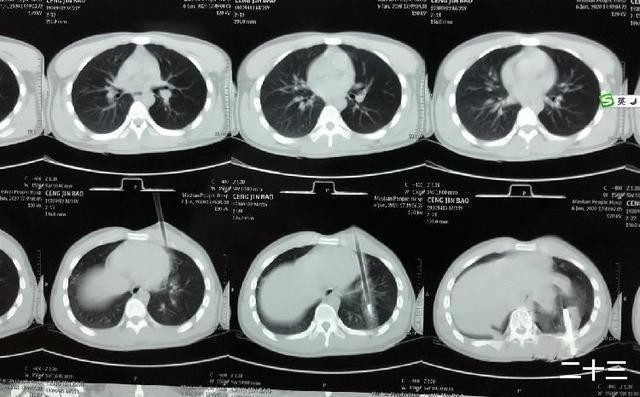

▼弓箭只離心臟1公分。(圖/翻攝自微博)

在手術當中,醫生發現,弓箭從左前胸緊貼著心臟,把上下肺都刺破了,距離心臟只有1公分,還把一根肋骨打斷後刺到了後背;當時傷情相當危險,不過因為弓箭沒有傷到心臟和大的血管,經過手術,病人已無大礙,現在恢復情況良好。

廣西南寧市一位年輕男子男子日前被弓箭射中胸口,慘遭「一箭穿心」。當時,他還在旁人的攙扶下,自己走到了醫院。醫院檢查後驚呆表示,弓箭射穿心口,距離心臟只有1公分,非常危險,「把肺刺破打斷肋骨穿背而出。」幸好,經過該院胸心腺體外科醫生1小時手術,弓箭被順利取出。